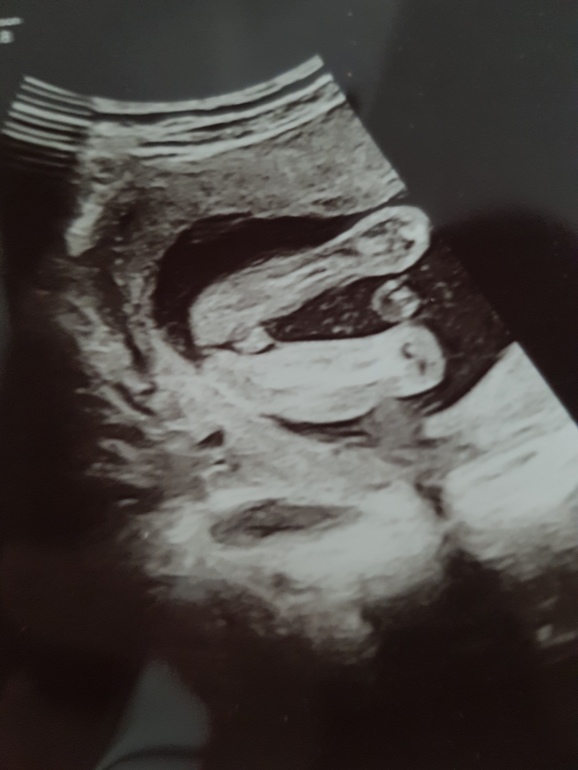

Сначала пообещали девочку, потом мальчика( фото прилагаю, но я думаю, что врач ошиблась), а сегодня малыш прятался и точно пол не сказали

Да видно что аппарат хороший по снимку,я не так давно пост выкладывала там девушка выкладывала похожее фото и писала что по узи была девочка а родился мальчик вот так бывает..)